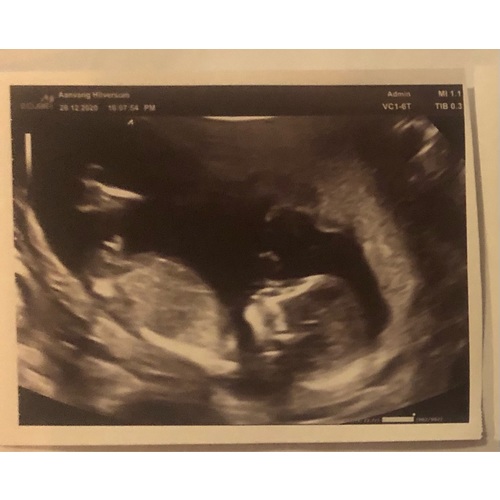

13 weken en 3 dagen, wat zien jullie?

Ik zou nog een keer kijken naar je foto's馃槈 Bij de ene foto twijfel ik maar ik gok toch 馃挋